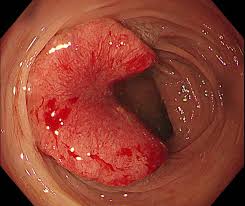

① 대장내시경 검사

가장 정확한 진단 방법은 대장내시경 검사입니다. 용종이 발견되면 절제 후 조직검사를 통해 암 여부를 확인할 수 있습니다.